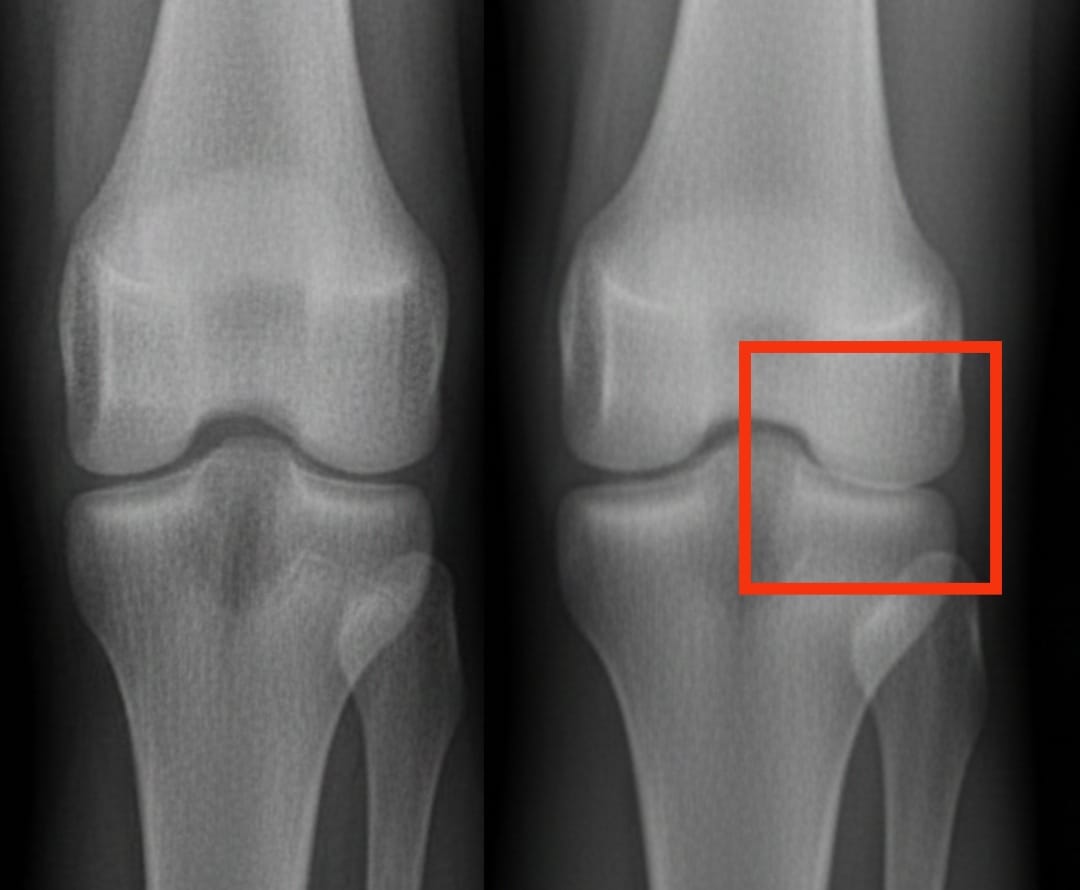

A artrose do joelho afeta centenas de milhões de pessoas em todo o mundo. Ela se caracteriza pelo desgaste progressivo da cartilagem, causando dores e dificuldades de movimento. Entre as soluções propostas, as injeções de plasma rico em plaquetas despertam um interesse crescente. Esse tratamento utiliza o próprio sangue do paciente, concentrado em plaquetas, para estimular a reparação dos tecidos e reduzir a inflamação.

Uma análise recente comparou a eficácia do plasma rico em plaquetas com a de outras injeções comuns: o ácido hialurônico, os corticoides e um placebo salino. Os resultados mostram que o plasma rico em plaquetas melhora significativamente a dor e a mobilidade após seis meses, com benefícios que persistem por até um ano. Essas melhorias são mais marcantes do que aquelas obtidas com o ácido hialurônico ou os corticoides, e bem superiores às do placebo.